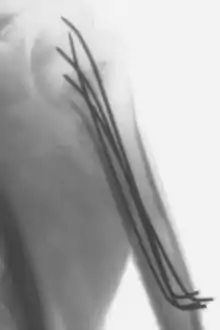

Intraoperative X-Ray of a humerus fixated by Kirschner wires